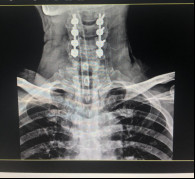

(術(shù)后拍片)

治療效果顯著康復(fù)出院

術(shù)后的康復(fù)漫長卻成效顯著,好消息一個(gè)個(gè)地傳來。在醫(yī)護(hù)人員的悉心治療下,病人癱瘓的右手患肢功能開始恢復(fù),已經(jīng)可以自主用勺子吃飯;2020年12月29日,手術(shù)后第25天,張阿伯可在腰帶保護(hù)下下地;2021年1月11日,張阿伯可以在家人的幫助下緩慢行走;術(shù)后44天,經(jīng)過近1個(gè)半月的康復(fù)治療,張阿伯已經(jīng)可以自行下地走路;2021年3月5日,張阿伯終于出院了。從瀕臨癱瘓困境中擺脫出來后,讓這個(gè)和諧幸福的家庭充滿了感激之情。

今年5月,張阿伯出院近2月后,大部分生活已經(jīng)可以自理。戈主任為張阿伯做了復(fù)查診治,結(jié)果顯示他的頸椎固定可靠,復(fù)位良好,病體正在朝理想的康復(fù)方向發(fā)展。